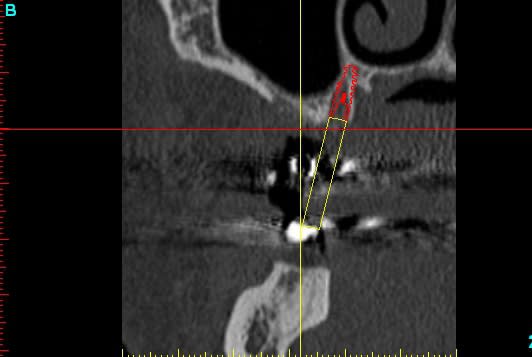

pour ceux qui m'ont demandé les images...;-)

la reconstruction 3D du scan

la planif avec le recalage du scan

la même en vue latérale avec le mapping osseux (mais qui devait merder, à cause de l'alim qui était en train de lâcher...)

et la radio post op...